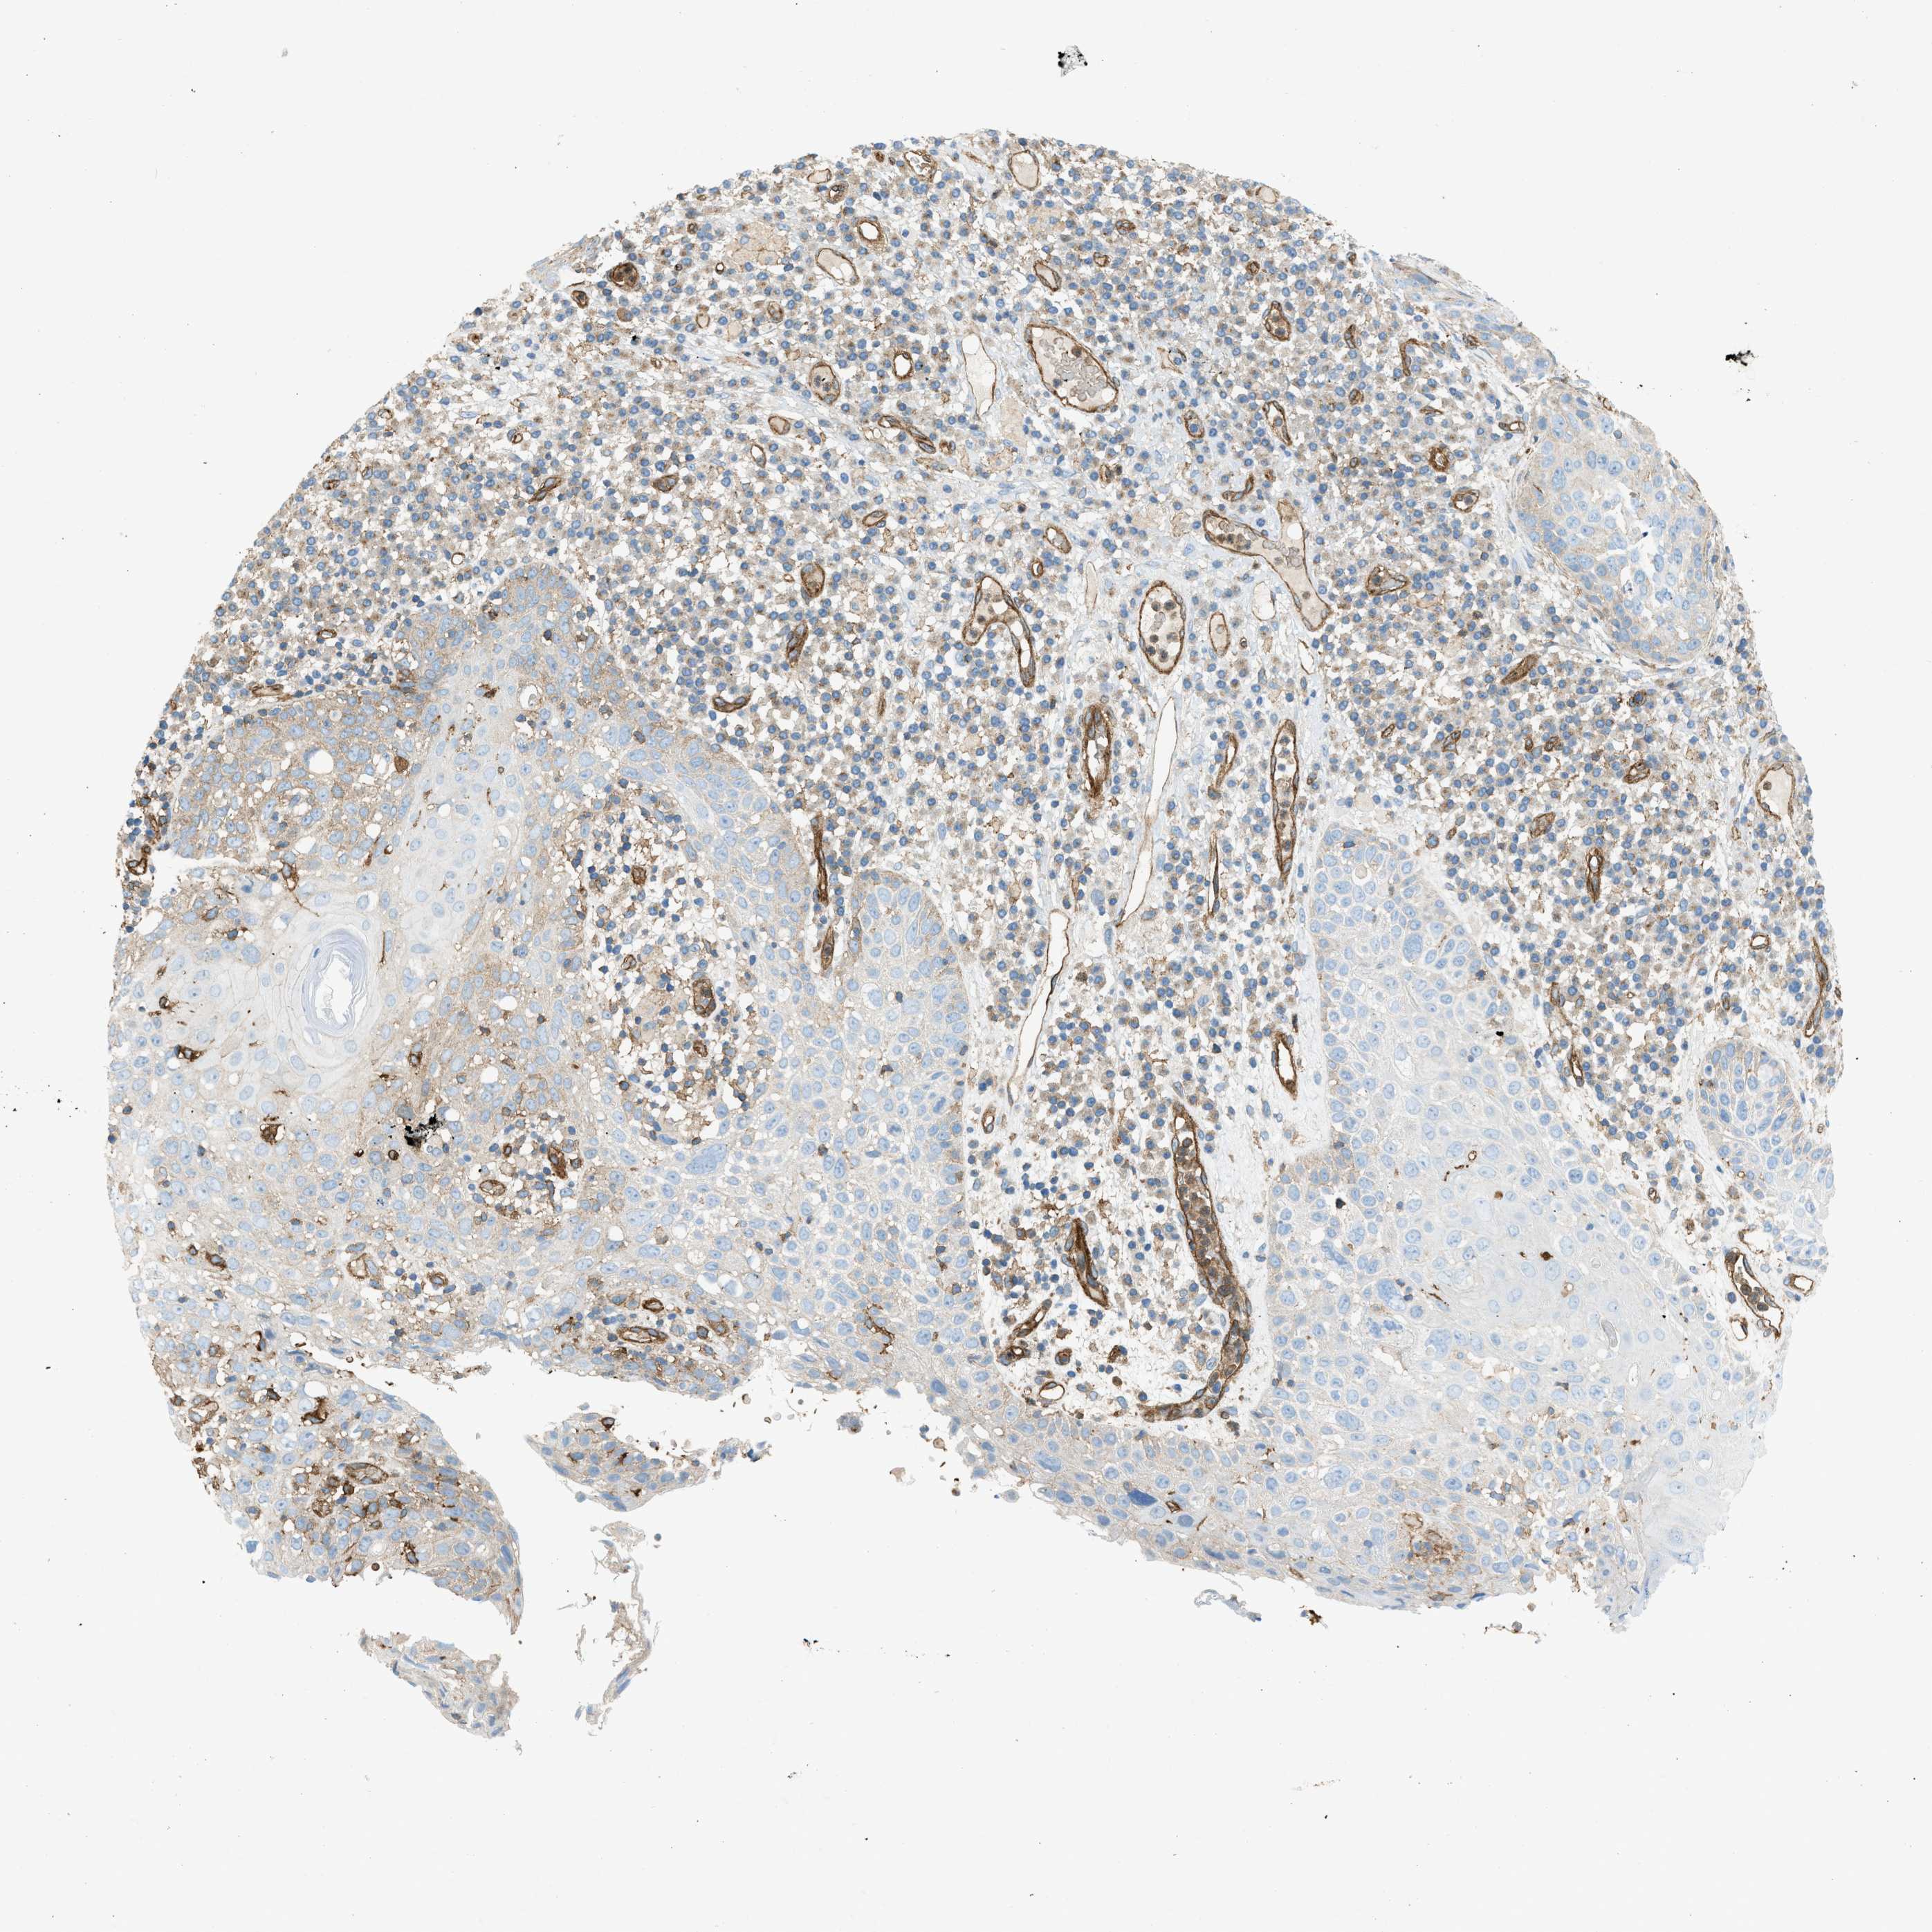

SKIN CANCER - Protein expressioni

A mouse-over function shows sample information and annotation data. Click on an image to view it in a full screen mode. Samples can be filtered based on level of antibody staining by selecting one or several of the following categories: high, medium, low and not detected. The assay and annotation is described here.

Antibody stainingi

Antibody staining in the annotated cell types in the current human tissue is reported as not detected, low, medium, or high, based on conventional immunohistochemistry profiling in selected tissues. This score is based on the combination of the staining intensity and fraction of stained cells.

Each image is clickable and will lead to virtual microscopy that enables deeper exploration of all samples and also displays staining intensity scores, fraction scores and subcellular localization as well as patient and tissue information for each sample.

Antibody CAB015334

Staining

High

Medium

Low

Not detected

Intensity

Strong

Moderate

Weak

Negative

Quantity

>75%

75%-25%

<25%

None

Location

Nuclear

Cytoplasmic/membranous

Cytoplasmic/membranous,nuclear

Squamous cell carcinoma in situ, NOS

Squamous cell carcinoma, NOS

Squamous cell carcinoma, metastatic, NOS